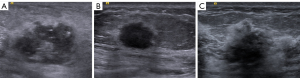

Blood flow was graded using the semi-quantitative Adler method (11). Grade 0: no blood flow signal detected in the mass; Grade I: sparse blood flow, with 1–2 visible dotted or short rod-like blood flows; Grade II: moderate blood flow, with 3–4 visible dotted blood flows or 1 long blood vessel, and the length of the latter can be close to or exceed the radius of the mass; Grade III: abundant blood flow, with >5 visible dotted blood vessels or 2 long blood vessels, as shown in Figure 1. The blood supply of all patients was divided into Grade 0–I and Grade II–III. Meanwhile, the ultrasound diagnosis for each patient was performed by two sonographers with more than 5 years of work experience, who should discuss any possible disagreements for a final decision.